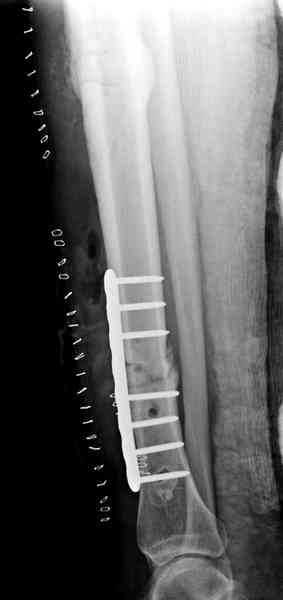

conference мы разбирали похожий случай, ложный сустав большеберцовой кости после резекции опухоли.

К нашему онкологу-ортопеду обратился больной с жалобами на боли в голени, из рассказа - год назад была сделана биопсия большеберцовой кости, но название заболевания "не запомнил”.

Оперирован в военном госпитале с заменой сегмента

аллокостью большеберцовой кости и после демобилизации явился для постоянного наблюдения по месту жительства.

В литературе "A Classic Adamantinoma Arising from

Osteofibrous Displasialike Adamantinoma in the Lower Leg: A case report and Review of the Literature похожие снимки.

Наши имели проблему со сращением, пришлось им сделать динамизацию, дополнительную аутопластику.

Снимки представлены.